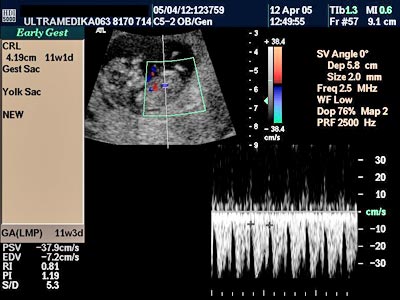

D) Četvrti UZ marker koji mora biti proveren je procena PI (pulzativnog indeksa) tj. procena otpora proticanju krvi kroz venski sud koji dovodi krv u srce ploda i naziva se Duktus venozus! Ova struktura je veličine nekoliko milimetara i pouzdano se može kodirati Braund Band CD i kolor Power Dopplerom. Praktično samo aparati velikih mogućnosti koji koriste ovu tehniku mogu u velikom procentu tj kod većine trudnoća u ovoj gestacionoj starosti registrovati patološki protok u Duktusu venozusu!

Inače patološki protok u ovom malom krvnom sudu je od velikog značaja jer može ukazivati da plod ima hromozomsku anomaliju ili urođenu srčanu manu!